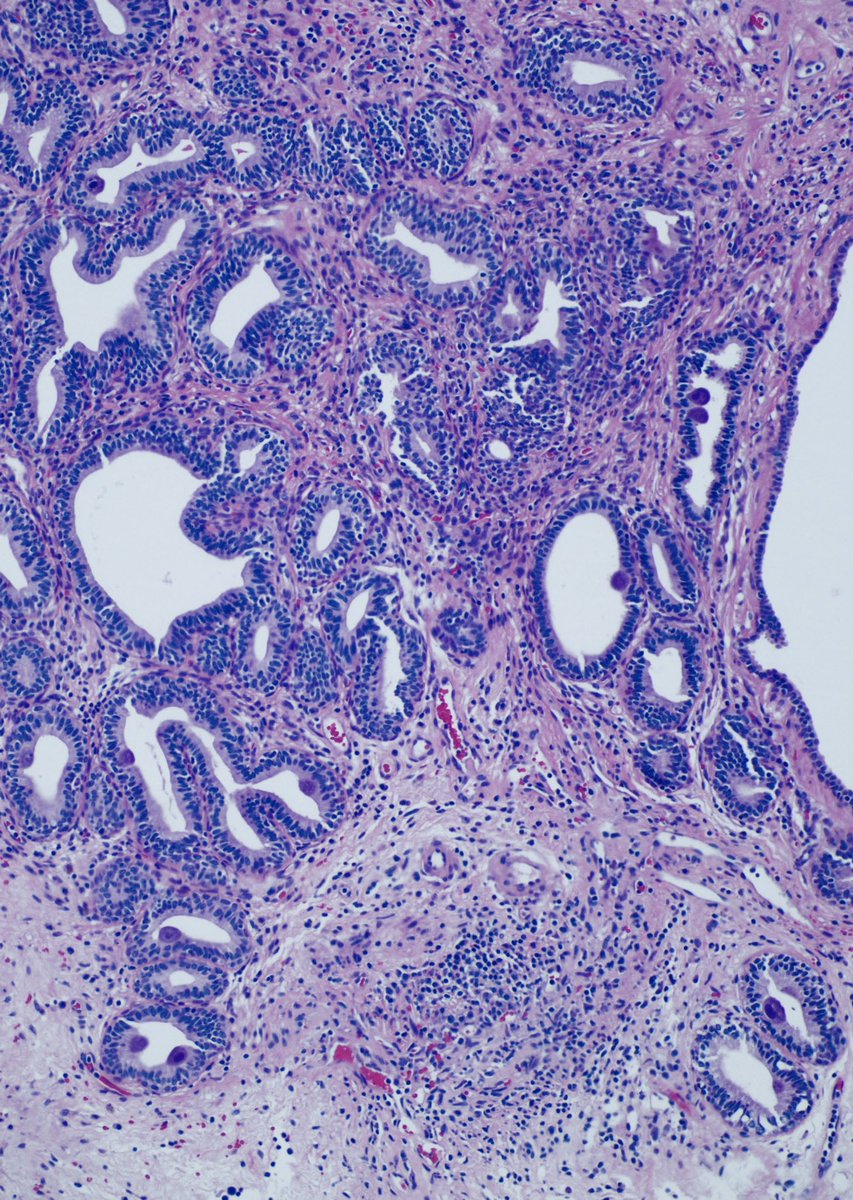

.

@StanfordPath Saturday!

30 YO woman returning from Zambia with hematuria. Cystoscopy shows a bladder “nodule”.

Acute and chronic cystitis with abundant eosinophils. Ova and helminths are seen.

#stanfordpathsaturday#IDpath#pathologytwitter#MedEdpic.twitter.com/ntcj5HUi7l